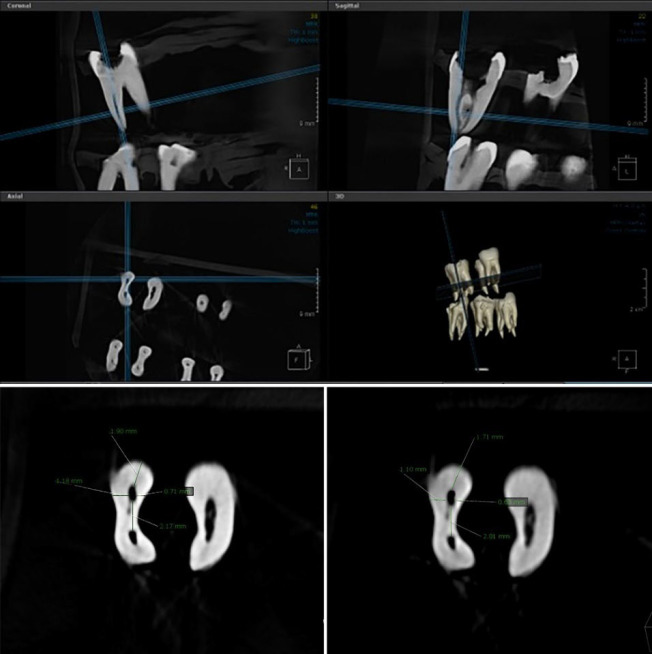

Materials and methods: This ex vivo study was conducted on curved (20-40 degrees) mesiobuccal canals of 60 mandibular molars. The teeth were randomly assigned to 4 groups (n=15) for instrumentation of the mesiobuccal canals with (I) TruNatomy, (II) EDMax, (III) Reciproc Blue, and (IV) Reciproc Blue+R-Pilot. Cone-beam computed tomography (CBCT) scans were obtained before and after instrumentation. Changes in canal wall thickness in mesiodistal (MD) and buccolingual (BL) directions were assessed at 1, 2, 3, and 4 mm from the apex using OnDemand software. Data were analyzed by the Kruskal-Wallis, Bonferroni, Friedman, and Fisher's exact tests (alpha=0.05).

Results: TruNatomy showed significantly lower transportation than Reciproc Blue and EDMax in the apical, middle, and coronal thirds (P<0.05). Reciproc Blue and EDMax had no significant difference in transportation (P>0.05). Using the R-Pilot glider had no significant effect on transportation (P>0.05). Canal transportation was not significantly different within each group at four distances from the apex (P>0.05). TruNatomy showed significantly higher centering ability than Reciproc Blue+R-Pilot in the BL dimension at 3 mm from the apex (P<0.05).

Conclusion: TruNatomy showed significantly lower canal transportation than Reciproc Blue and EDMax at all distances from the apex. The files had no significant difference in centering ability except at 3 mm in BL dimension, where TruNatomy had significantly higher centering ability than Reciproc Blue+R-Pilot.